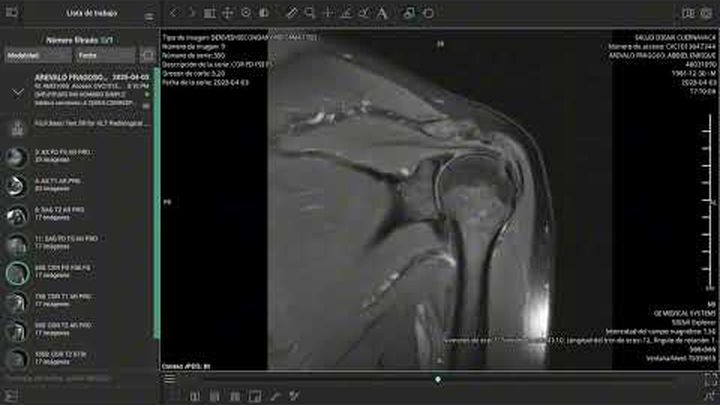

El pasado 2 de marzo de 2025, sufrí un accidente en carretera mientras conducía mi motocicleta. Un automóvil me impactó y me arrojó contra el asfalto, causándome lesiones severas en el hombro izquierdo, columna cervical y lumbar. El conductor se dio a la fuga, y hasta ahora no ha sido posible obtener justicia ni apoyo institucional.